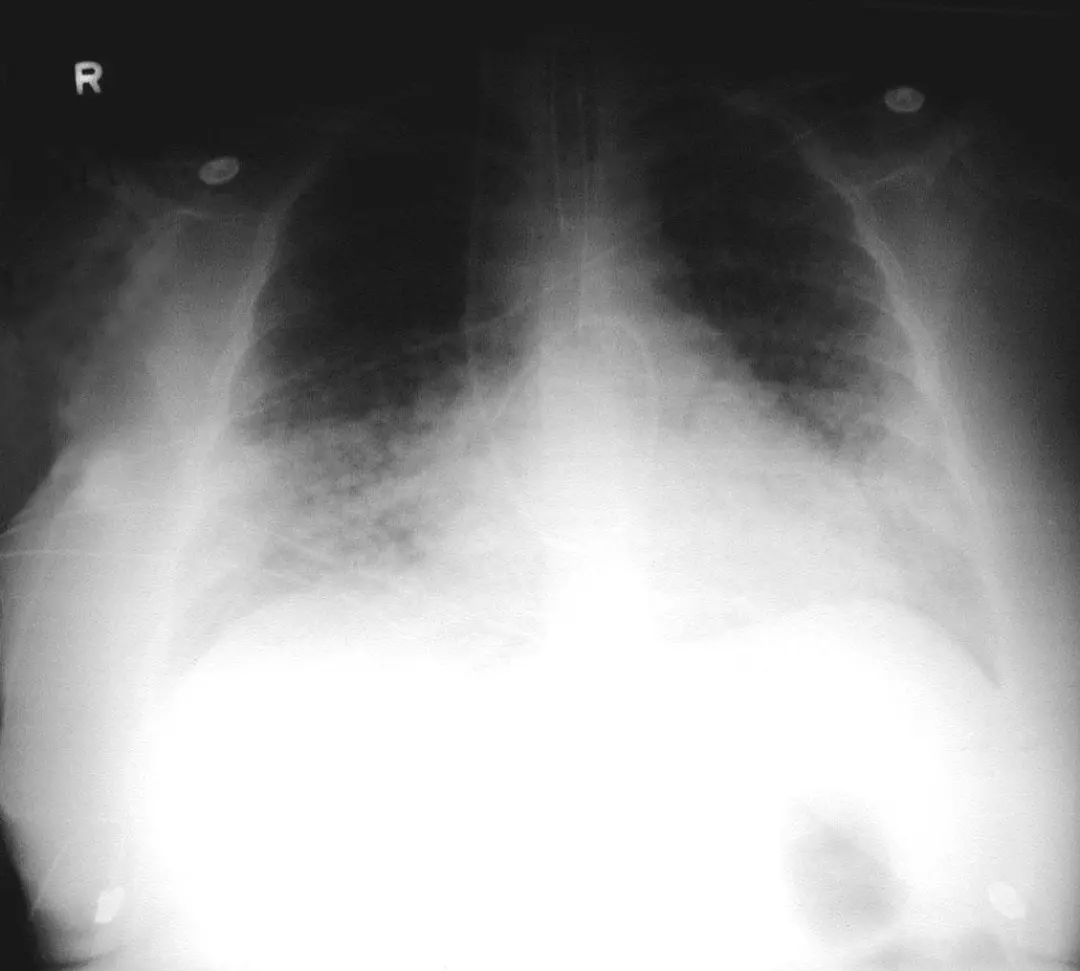

图1.1 细菌性肺炎。右上叶肺炎患者的放射影像。胸廓前后径增大,提示有慢性阻塞性肺疾病(COPD)。

图1.2 细菌性肺炎。双肺下叶肺炎患者影像。